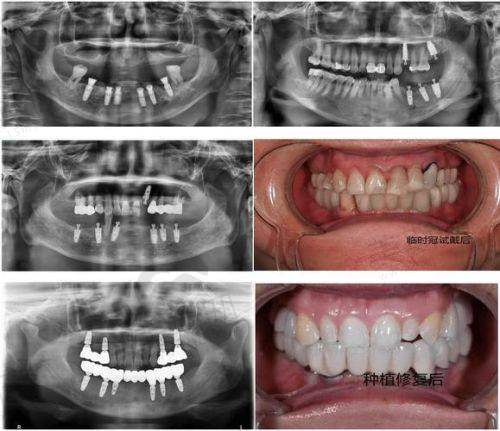

湖南省娄底市娄星区景辰口腔医院的核心特色技术为数字化精细种植技术,该技术整合了CBCT三维成像、计算机辅助设计(CAD)、3D导板打印等前列科技,实现种植手术的“可视化、精细化、微创化”。具体优势如下:

首先,术前通过德国西诺德CBCT机进行口腔扫描,获取牙槽骨密度、高度、宽度等三维数据,精度达0.1mm,医生可在计算机上模拟种植过程,避开神经及血管,制定个性化种植方案。其次,根据模拟方案3D打印种植导板,术中无需翻瓣,直接通过导板精细植入种植体,手术时间较传统种植缩短40%,单颗种植仅需15 - 30分钟。再者,采用瑞士士卓曼、瑞典诺贝尔等国内外有名种植体,生物相容性好,骨结合速度快,部分患者可实现“即刻种植、即刻修复”,当天戴牙。

该技术尤其适用于牙槽骨条件复杂、对手术精度要求高的患者,自开展以来已成功完成2000余例种植手术,术后并发症发生率低于1%,患者满意度达98%。此外,医院还建立了种植术后跟踪体系,定期回访患者修复情况,提供终身维护服务,确保种植体长期稳定使用。